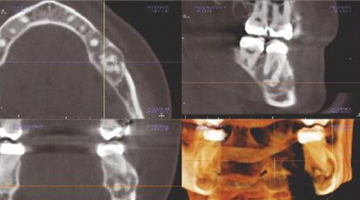

Above: Images from the Carestream Dental CS 9300